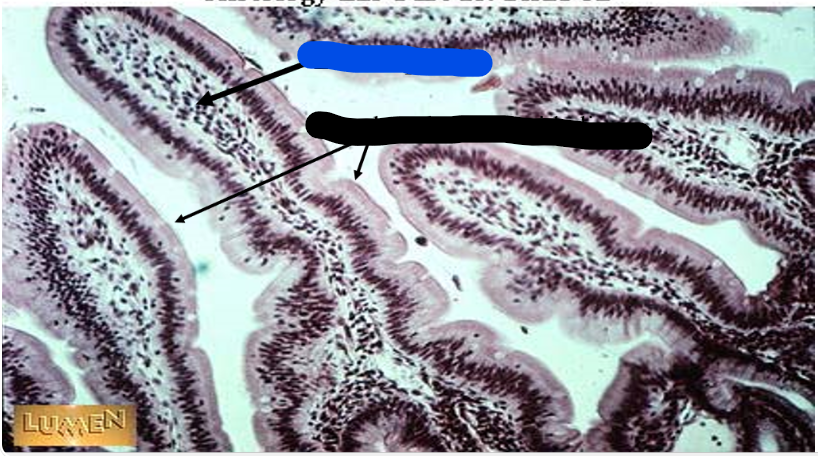

plicae circulares

green

villi

crypts

blue

lamina propria

black

simple columnar epithelium